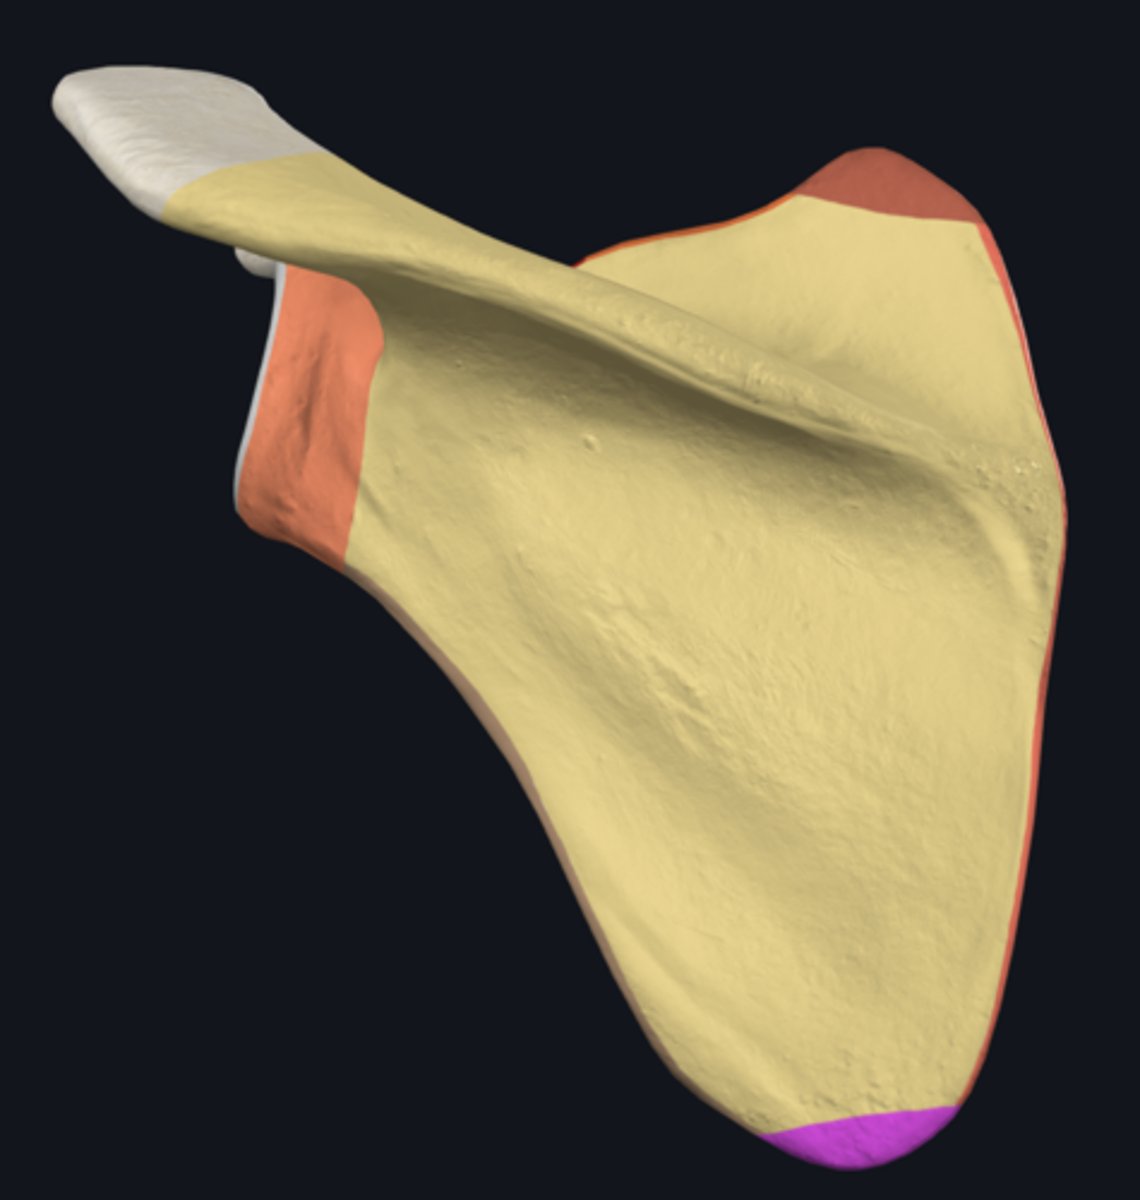

Acromion

Superior angle of scapula

Coracoid process

lateral border of scapula

medial border of scapula

inferior angle of scapula

body of scapula

Head of scapula

neck of scapula

costal surface of scapula

lateral angle of scapula

posterior surface of scapula

scapular notch

superior border of scapula

acromial angle

clavicular facet

glenoid fossa

infraglenoid tubercle

infraspinous fossa

spine of scapula

supraglenoid notch

subscapular fossa

supraglenoid tubercle

supraspinous fossa